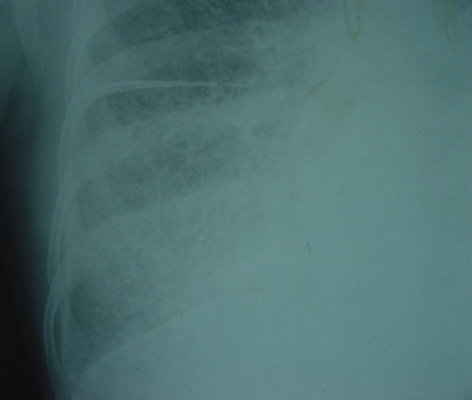

女性,22岁,体检病例.结果:http://www.radida.com/bbs/forum.php?mod=viewthread&tid=15784

诊断:家族性肺泡微结石症

诊断依据:1、胸片可见弥漫性细针尖高密度影;2、 水平裂,右侧胸膜,左侧心包膜钙化;3、肺野透亮度自肺尖至下肺野明显减低;4、临床症状和胸部x线表现不相称;5、动员其家庭成员胸片检查,再次发现其同胞姐姐胸部有相同表现(八十年代没ct);6、随访至今两姐妹生活良好,临床症状稍显加重。

肺泡微结石症较少见,病因尚不明。病理改变:(1)肺泡腔内可见无数呈同心圆排列的微小结石,直径0.01~3.0 mm。少数微石位于肺泡壁或肺间质内。肺泡内无炎性反应。(2)肺泡壁早期正常,随病程进展可有炎性细胞浸润和间质增生,晚期间质纤维化和巨细胞形成使肺泡壁增厚,并发生肺大泡。(3)病程晚期可并发肺动脉高压和肺源性心脏病。部分病例有家族性,多数病例均无局部或全身症状,但在晚期病例,由于肺功能不全,在运动后有气急,逐渐发展到呼吸困难,并有紫绀、咳嗽、咳痰等。病程多缓慢,10-20年不等。x线表现为两肺满布细小沙粒状阴影,直径为0.3-1mm,密度很高,超过肋骨密度,边缘光滑,形态不规则。此种沙粒状阴影多孤立,不融合,下肺野较上肺野为多。hrct表现:(1)粟粒状结节钙化影:表现为两肺弥漫性分布的钙质细粒,直径1~2 mm,边缘清楚,部分可融合成较大结节。(2)线状钙化影:指位于脏层胸膜下的肺表面薄层线状钙质沉着,多见于舌段和中叶的前外侧面。此外可见胸膜和心包增厚及钙化。(3)肺大泡和肺气囊:为多发的沿胸膜下分布的含气囊腔影,破裂后可合并气胸。(4)网状条索影:为晚期肺间质纤维化的表现。(5)肺内病变进展缓慢,可维持十几年无明显改变。

鉴别诊断:粟粒型肺结核、矽肺、转移瘤等